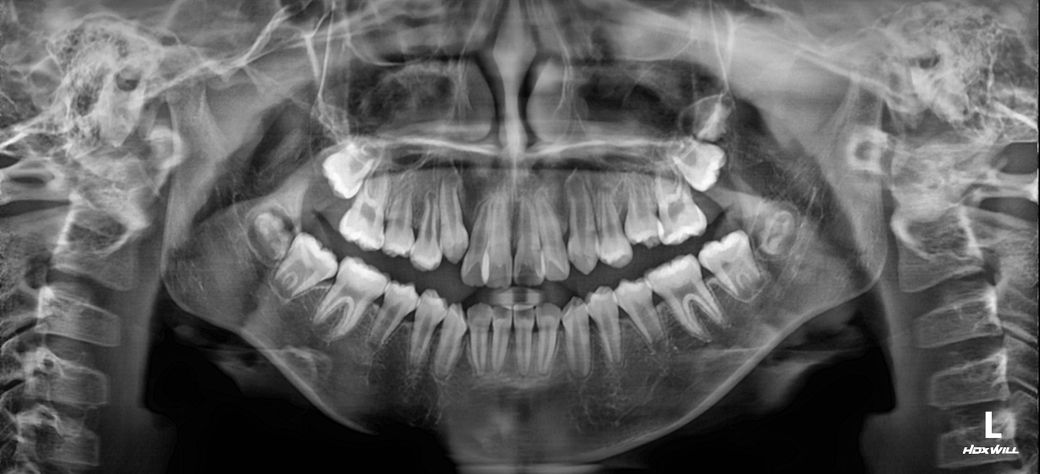

중1 여자 아이 교정진단 부탁드립니다.

앵글씨 몇급인지 궁금합니다.

의사 선생님마다 소견이 다르셔서 혼란 스럽네요.중1 여자 아이구요.시기적으로 지금 교정을 시작하기에 적절한지 궁금합니다.

• 1번 째 사진

앵글 2급 부정교합이며, 지금 교정하는 것이 좋을 것으로 보입니다. 더 늦어지면 교정이 까다로워 질 수도 있습니다. 지금 현재도 쉬운 케이스는 아닙니다.

앵글씨 부정교합측면에서 보면 1급인거 같고 치열이 좋지 않아서 중학교 1학년이면 교정을 시작하셔도 괜찮을 시기인거 같습니다.